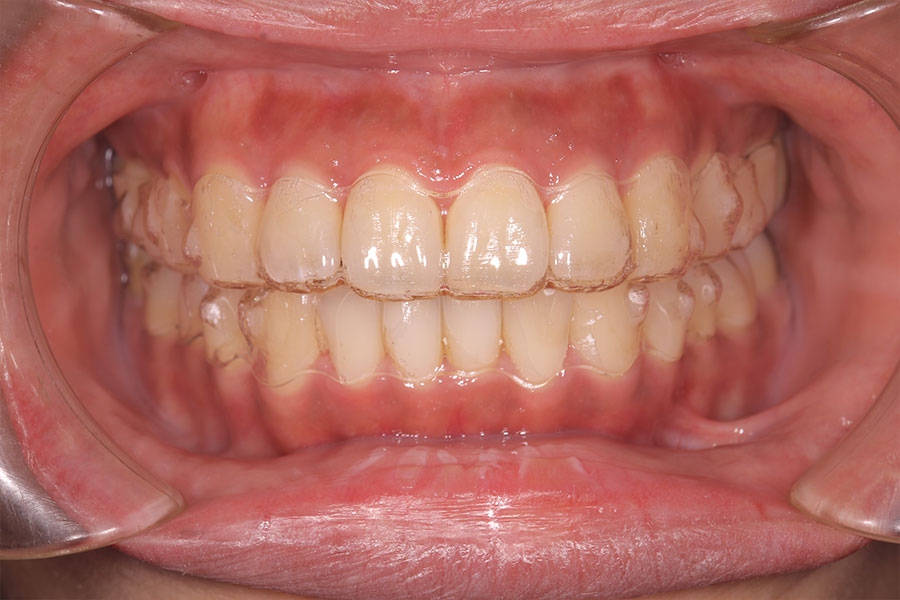

Before -正面-

After -正面-

Before -側面-

After -側面-

| 施術内容 | ワイヤー矯正から、目立ちにくくメタルフリーなインビザラインへ変更しました。 金属アレルギーの不安が軽くなり、取り外しできることで清掃性も向上。見た目も自然で、治療中のストレスが少ない矯正方法です。 |

|---|---|

| 治療期間 | 2年間 |

| 費用 | インビザラインフル 767,800円 リテーナー 30,000円 |

| リスク・副作用 | 治療にともない、歯の破折や歯質の削合、場合によっては抜歯が必要となることがあります。また、金属や補綴物を除去する際に、完全に除去できない場合もあります。 |